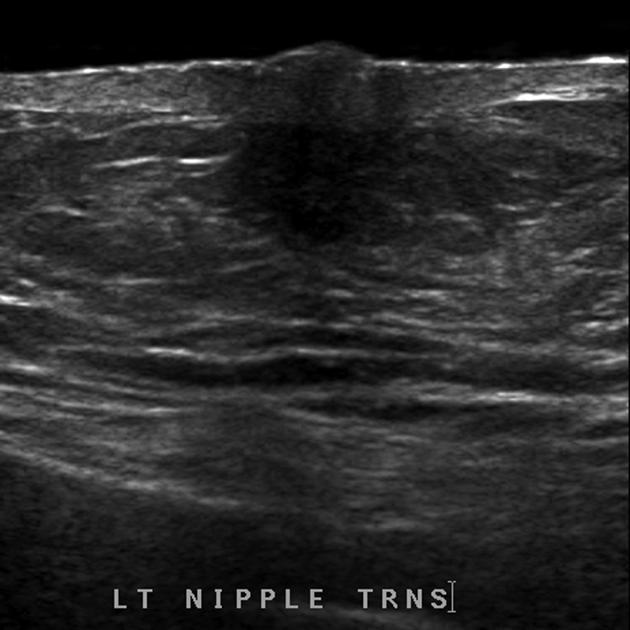

Duct ectasia

Abnormal duct widening >2mm

- Due to benign or malignant process

• Benign: chronic inflammatory + fibrotic changes → thickening of debris → calcification

• Malignant: intraductal malignancy

• *Branching tubular structures >2mm**

• Anechoic or echogenic (inspissated secretions) contents